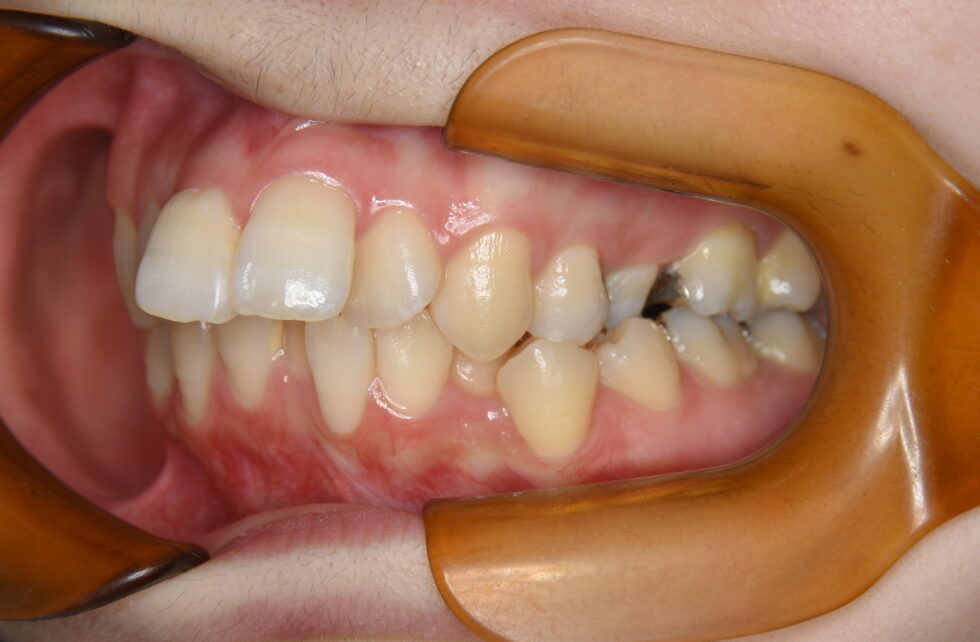

初診時年齢29歳の女性。前歯の叢生を伴う上顎前突のケース。

前歯の叢生と前傾を気にして来院されました。

上顎左右側第一小臼歯、下顎左右側第二小臼歯の抜歯を行って頂き、マルチブラケット装置と矯正用インプラントアンカーを使用して動的治療を行いました。

前歯の叢生を改善し、前歯の後退により口元の形態も整えることが出来ました。